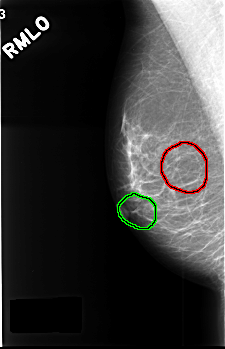

C_0386_1.RIGHT_MLO

FILE: C_0386_1.RIGHT_MLO.OVERLAY

TOTAL_ABNORMALITIES 2

ABNORMALITY 1

LESION_TYPE MASS SHAPE OVAL MARGINS CIRCUMSCRIBED

ASSESSMENT 3

SUBTLETY 5

PATHOLOGY BENIGN

TOTAL_OUTLINES 1

BOUNDARY

ABNORMALITY 2

LESION_TYPE MASS SHAPE LOBULATED MARGINS CIRCUMSCRIBED

SUBTLETY 4